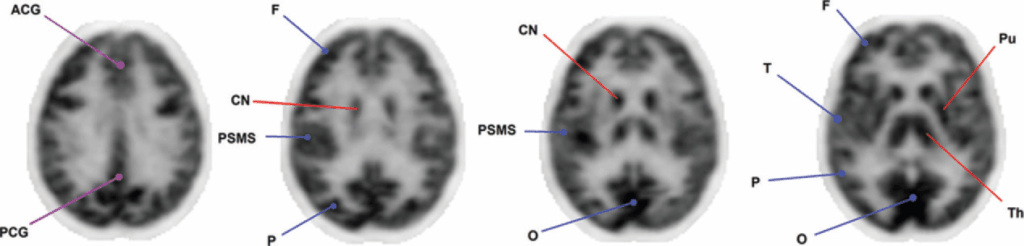

In un soggetto sano, la biodistribuzione del FDG nel cervello segue una gerarchia di intensità di captazione ben definita:

- captazione più intensa: si osserva a livello del putamen, del nucleo caudato, del talamo e della corteccia di materia grigia;

- captazione lieve: il globo pallido mostra tipicamente una captazione di intensità moderata.

- bassa captazione: la sostanza bianca presenta la più bassa attività metabolica.

Abbreviazioni:

ACG = giro cingolato anteriore

CN = nucleo caudato

F = lobo frontale

O = lobo occipitale

P = lobo parietale

PCG = giro cingolato posteriore

PSMS = striscia sensori-motoria primaria

Pu = putamen

T = lobo temporale

Th = talamo